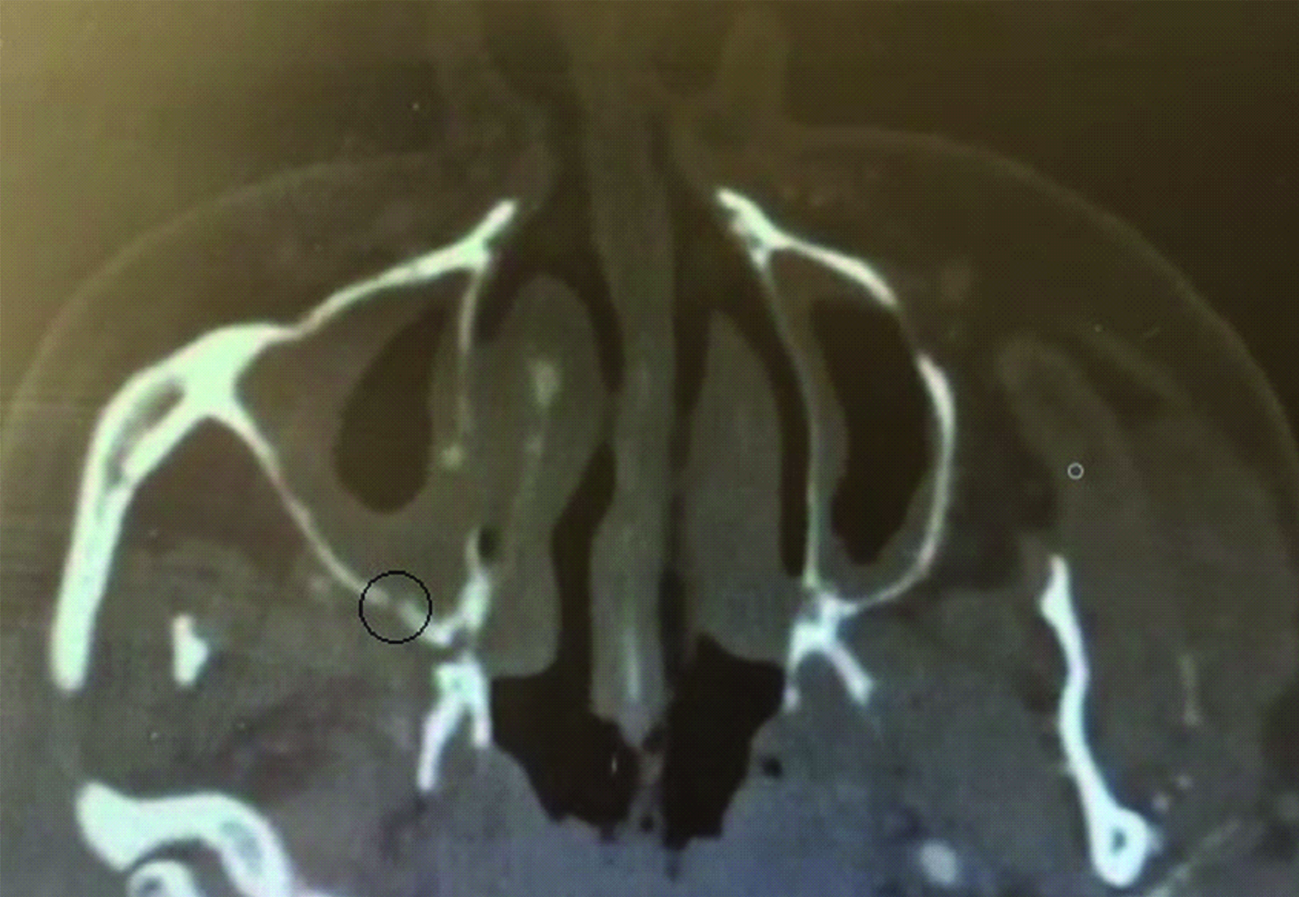

30.03.2016 было выполнено контрольное КТ ОНП в условиях поликлиники для оценки динамики состояния после оперативного вмешательства – визуализирован пристеночный отек верхнечелюстных пазух справа и слева, ярко выражен дефект задней стенки правой верхнечелюстной пазухи (рисунки 2, 3).

Рисунок 2. КТ околоносовых пазух от 30.03.2016. Сохраняется пристеночный отек верхнечелюстной пазухи, костный дефект задней стенки правой верхнечелюстной пазухи.

Figure 2. CT imaging of the paranasal sinuses dated 30.03.2016. The parietal edema of the maxillary sinus persists, as well as a bone defect in the posterior wall of the right maxillary sinus.

Рисунок 3. КТ околоносовых пазух от 30.03.2016. Сагиттальный срез. Ярко выраженный костный дефект задней стенки верхнечелюстной артерии.

Figure 3. CT imaging of the paranasal sinuses dated 30.03.2016. Pronounced bone defect in the posterior wall of the maxillary artery. Sagittal section. Pronounced bone defect in the posterior wall of the maxillary artery.